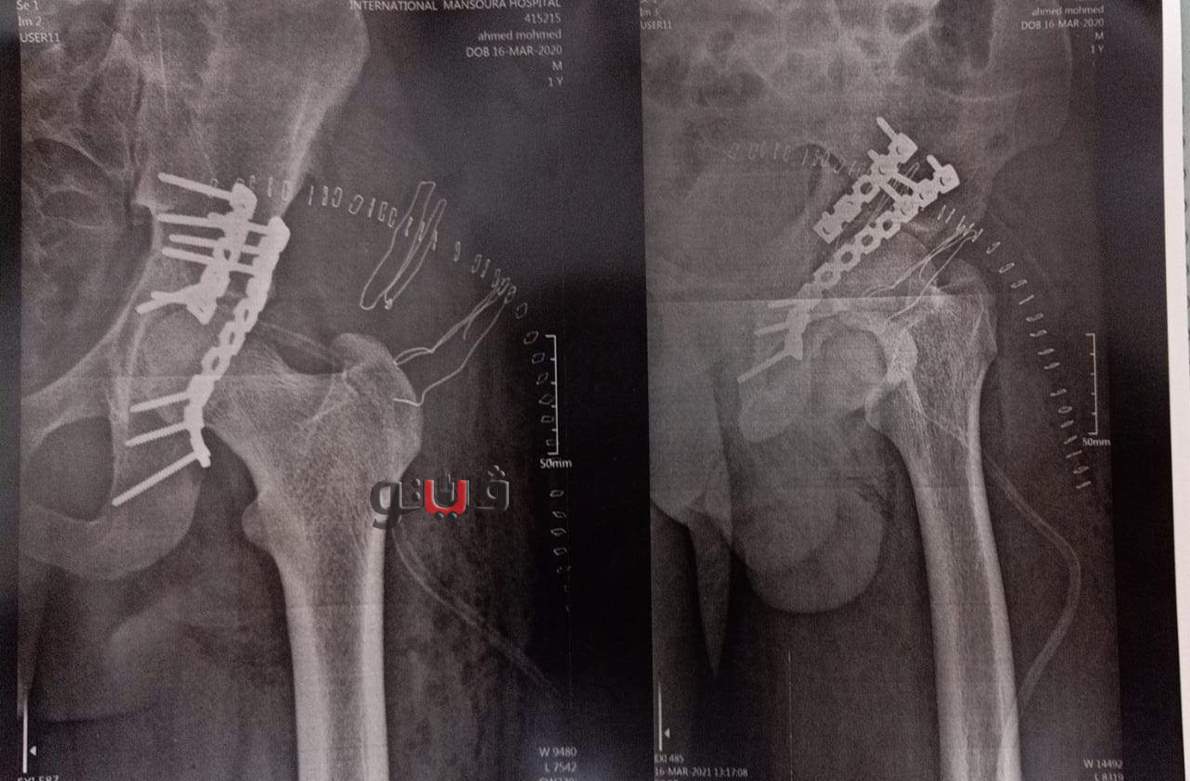

أعلن الدكتور سعد مكي وكيل وزارة الصحة بالدقهلية عن نجاح فريق طبي في إنهاء معاناة شاب يبلغ من العمر 20 عاما كان يعاني من كسر بحق مفصل الفخذ الأيسر مع خلع بالمفصل مع تأثر العصب الوركي وتمكن الفريق الطبي من إجراء جراحة عاجلة لرد الخلع وتثبيت الكسر بشرائح ومسامير معدنية وعمل استكشاف للعصب الوركي.

الطاقم الطبي الدكتور حسن وهدان استشاري جراحة العظام والمفاصل، الدكتور محمد جودة طبيب مقيم جراحة العظام

الدكتور عبد الرحمن استشاري التخدير، وفريق التمريض محمد طلبة تمريض، مصطفى الشرقاوي تمريض، ومحمد الشحات فني عظام.